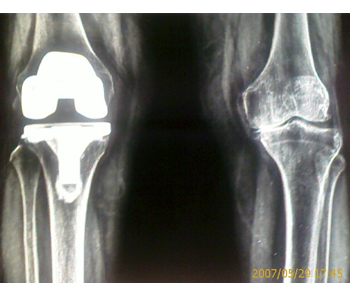

Our patients get excellent alignment on x-rays |